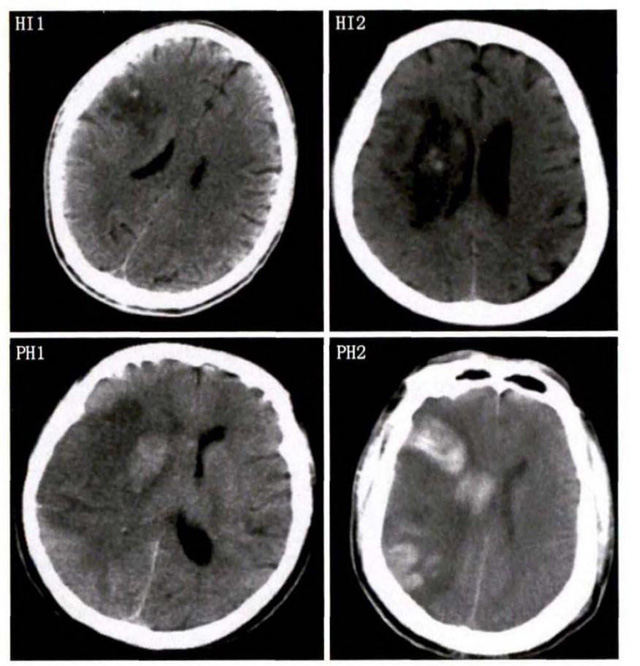

中、老年病患,有动脉粥样硬化及高血压病等脑卒中的危险因素,发病结合神经系统症状和体征,应当考虑急性脑梗死的可能。再经脑CT/MRI发现梗死灶,或排除脑出血、炎症性疾病等,诊断即可确定。脑梗死有时颇似小量脑出血的临床表现。脑栓塞在任何年龄都可以有发病的风险,可以在几秒到几分钟达到顶峰?;嵊衅辈荒芩祷暗染植可窬δ芩鸹怠Kㄗ永丛春苤?,可能是冠心病、心肌梗塞、心内膜炎等。合并心房纤颤,结合其他脏器官的支持诊断,CT跟磁共振都可以检查确定栓塞位置数量还有是不是有伴发出血等问题??梢园镏锒稀?/span>

中老年有高血压糖尿病发病病史,起病神经功能缺损症状,临床表现为腔隙综合征,即可初步诊断本病。如果CT或磁共振证实有与神经功能缺失一致的脑部腔隙病灶, 符合大脑半球或脑干深部的小穿通动脉病变,即可明确诊断。少数患者隐匿起病,无明显临床症状,在影像学检查时发现。